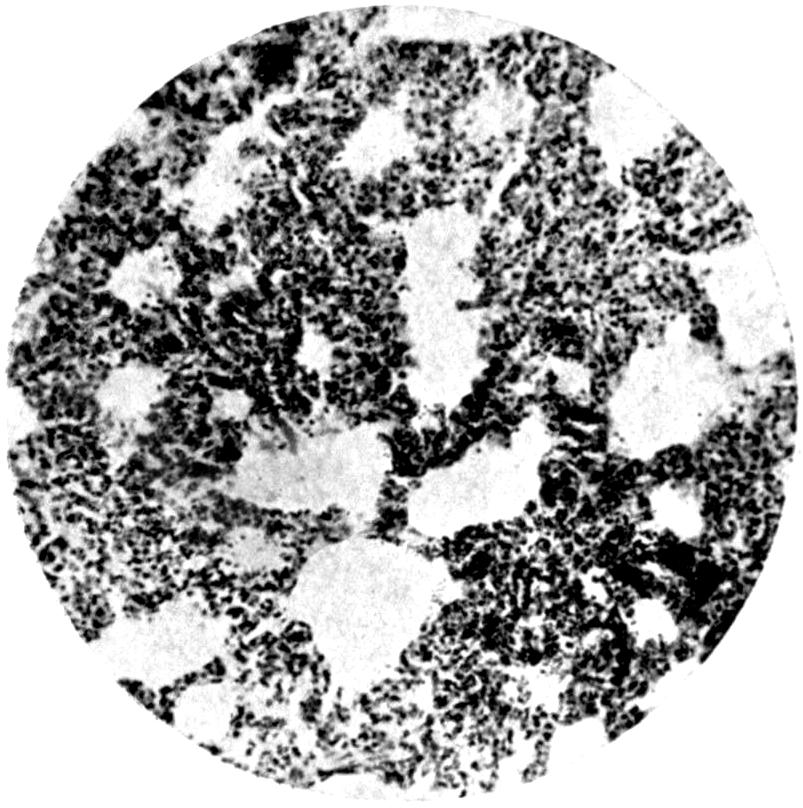

Plate IV. 276